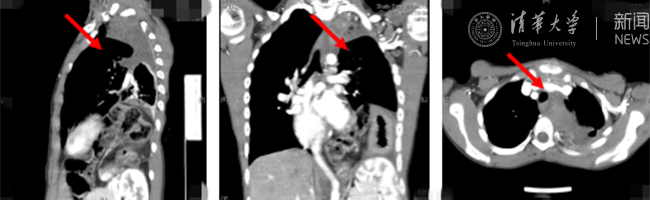

mk(中国)网8月30日电(通讯员 杨峰)如图中所示,本是正常人心脏、左肺的位置,被发于神经鞘的巨大肿瘤占据,导致一位刚满12岁的男孩胸痛、咳嗽、呼吸困难。近日,北京清华长庚医院神经外科与胸外科联手,由神经外科王贵怀主任主刀,成功为男孩切除胸腔巨大神经鞘肿瘤。

患者胸腔内巨大的肿瘤。

半年前,患者经常会出现胸痛、咳嗽和呼吸困难,在当地医院检查发现左侧胸腔巨大占位,左肺及心脏明显受压。王贵怀大夫接诊,仔细查体了解病情,并反复认真阅片后,认为左侧胸腔巨大肿瘤来自于胸椎椎管内,神经鞘瘤可能性大。该肿瘤体积巨大,占据绝大部分胸腔空间,压迫左肺、纵隔大血管及膈肌。